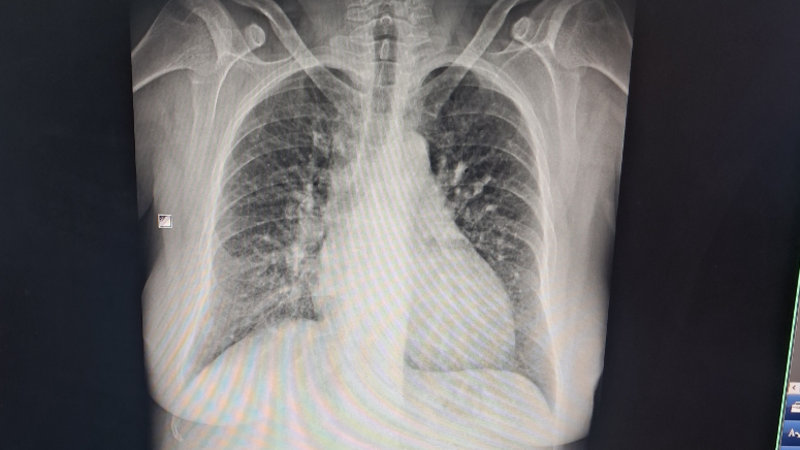

Meu nome Alessandro muitos me conhecem como Bicho, alguns sabem do problema de saúde da minha esposa e outro irão  saber agora, ela doente renal crônica grave. Nao tem os 2 rins e o que foi transplantado perdeu em janeiro de 2024, adiquiriu dentre a doença um problema de coração (angina) e hoje dia 28 de agosto de 2024 fui a upa de iraja com ela para atendimento na emergência e alem disso descobrimos que ela está com coração grande alem do normal, muito avançado e vem comprimindo seu pulmão e dando falta de ar nos deixando por várias noites em claro. Elá precisa fazer exames pra saber a dimensão do problema para qué possamos voltar ao Cardiologista e a espera do SUS e incansavel e sem previsão para o exame e com essa espera nao sei o quanto ela suportaria esperar. E como todos sabem sou um taxista auxiliar, pago diaria, aluguel, agua, luz e etc… e ainda nao recebemos auxílio pois o dela foi cortado em 2019 dado como apta ao trabalho e recorremos e perdemos pois o juiz negou, enfim nossa justiça enquanto tem tantos que precisam e nao recebem e tem tantos que recebem e nao precisam, e infelizmente nao tenho condições de pagar isso tudo, ou venho aqui peco ajuda mesmo envergonhado ou perco a vida da minha esposa para doença.